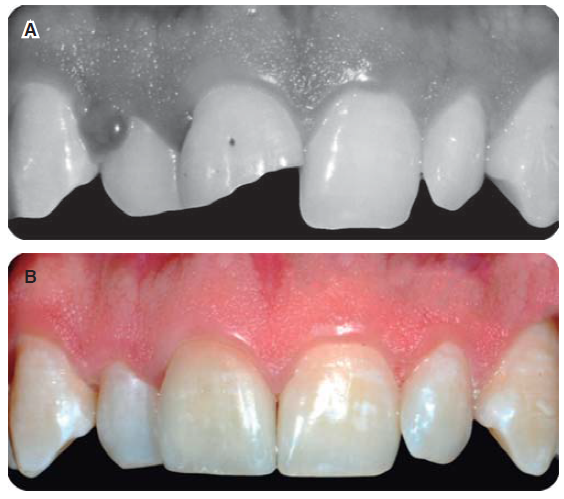

Restauración final (disilicato de litio estratificado)

La restauración de disilicato de litio estratificado (IPS e.max ®, Ivoclar Vivadent ©) fue cementada con Variolink ® N, previo tratamiento para un protocolo de adhesión, siendo grabada por 20 segundos con ácido fluorhídrico al 9%, lavado con agua en espray por 20 segundos y sumergida en una solución de bicarbonato de sodio para neutralizar el efecto del ácido, lavada y secada para continuar silanizando por 60 segundos.25 El ataque químico disuelve la estructura cristalina y permite la retención adicional de los bloques con silano y cemento de resina.23,26

La superficie de la preparación fue acondicionada con ácido fosfórico al 37% por 15 segundos, se lavó con agua en espray, se secó y aplicó el adhesivo ExciTE F DSC, para continuar con la mezcla del Variolink N (Base) para aplicarlo en la corona, llevarla a su posición final eliminando excedentes y polimerizando por 10 segundos para verificar que no existan excedentes del material cementante que comprometan la salud periodontal, finalizando con una polimerización por 20 segundos (Figuras 25A y 25B).23

Restauración final

Se optó por utilizar cerómero (Adoro).27,28 Fue cementada con Variolink II color A3, previo tratamiento de la restauración para protocolo de adhesión, siendo acondicionada con ácido fosfórico al 37%, lavado con agua en espray por 20 segundos, secada para continuar silanizando por 60 segundos (Monobond S, Ivoclar Vivadent) para facilitar la unión química. Después de limpiar el muñón, se aplica gel de ácido fosfórico al 37% y se deja actuar por 20 seg. Se elimina el gel con agua y se seca el exceso de humedad de tal forma que se aprecie una superficie de dentina que no se encuentre deshidratada (Figura 32).

Se satura el esmalte y la dentina con una abundante cantidad de Excite DSC, eliminando ligeramente el sobrante y el solvente (alcohol) se evapora con aire.

El sobrante del material resinoso usado en la cementación, se elimina de la restauración en estado blando o parcialmente polimerizado; por ejemplo, con ayuda de un pincel monouso o esponja dental, se debe polimerizar el Variolink II con una lámpara de alta intensidad (900 mW/cm2), el tiempo de exposición con esta potencia es de 40 seg por segmento (Figura 33).